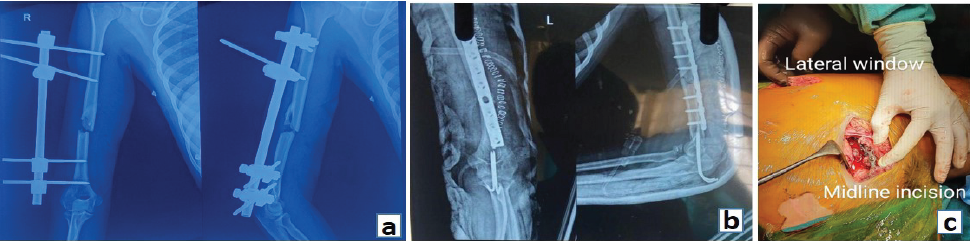

Management was planned as per the principles of EAC. On June 25th, 2022, the following fractures were managed under general anesthesia in the same sitting:

- Wound debridement and fracture stabilization of the right arm were done with an external fixator (Fig. 2a)

- For elbow dislocation, closed reduction and trans-olecranon fixation with two K-wires was done (Fig. 2b)

- Open reduction and internal fixation (ORIF) of the left humerus fracture was done with a limited-contact dynamic compression plate (LCDCP) through posterior approach (Fig. 2b)

- As the left acetabulum was also fractured along with the shaft of the femur, retrograde femur nailing was done.

Figure 2: (a): Post-operative X-ray showing stabilization of right humerus with an external fixator, (b) Post-operative X-ray showing trans-olecranon fixation of the left elbow and internal fixation of left humerus fracture with limited-contact dynamic compression plate. (c) Intra Op image showing acetabulum fracture fixation through Modified Stoppa Approach.

In the second sitting on June 29th, open reduction and pubic symphysis plating was done along with anterior column buttress plating through a modified Stoppa approach to address both the acetabulum and rami fracture simultaneously (Fig. 2c). On July 15th, 2022 the external fixator was removed from the right upper limb; pin sites were healthy. ORIF of humerus fractures were done with 4.5 mm LCDCP through a posterior approach. From the left elbow, K-wires were also removed, and above-elbow support was given for the next 6 weeks. The patient was advised to perform passive and active range of motion exercises in the right elbow and shoulder, and left hip and knee from the 1st post-operative day. The patient was advised to complete non-weight-bearing on the left lower limb for 6 weeks. After 6 weeks, partial weight-bearing was advised with walker support, the slab was removed and left elbow and shoulder range of motion exercises were started. After 3 months, complete weight-bearing was allowed. Active quadriceps, hamstrings, and hip abductors strengthening exercises were also advised. The patient was followed up at regular intervals for a period of 2 years to assess functional and radiological outcomes. After 6 months, the patient was able to do all her daily routine activities. The patient regained her pre-trauma level of activities by the end of 1 year. On the past visit at 2 years, the patient had satisfactory radiological (Fig. 3a and b) and functional outcomes (Fig. 4). Her Harris hip score was 97. The bilateral elbow range of motion was adequate without any instability.